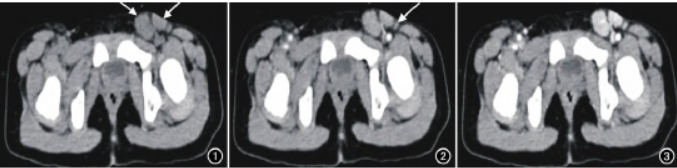

图1 腹股沟CT平扫示左侧腹股沟区多发类圆形软组织密度肿块影,密度均匀,边界清楚,CT值约42HU(箭)。 图2 CT增强扫描动脉期示病灶呈轻度均匀强化,CT值约61HU,病灶周围可见“卫星灶”(小淋巴结)(箭)及迂曲的供血动脉。 图3 增强扫描静脉期示病灶进一步明显强化,CT值约117HU。图4 增强扫描延迟期强化程度减低,CT值约98HU。 图5 CT冠状面上可见多发肿大的类圆形软组织肿块部分融合,增强呈显著强化,强化程度同邻近大血管。

部分病灶周围可见滋养血管及反应性增生的小淋巴结构成的“卫星灶”。增强扫描的病灶强化程度及方式与病理类型密切相关,HV-CD可见滤泡间区大量增生微小动脉及滋养血管,因此动脉期显著强化,与邻近大血管强化方式基本同步,类似血管样强化较典型,而肿块内细小血管常增厚,发生透明样变性,致血液在微循环停留时间延长,故呈快进慢出型,渐进性强化。

MRI上CD多呈境界清楚的软组织肿块影,T1WI呈等或稍低信号,T2WI序列信号较多变,可能与病灶内坏死囊变、纤维化和钙化所占的比例有关,呈等、稍高或高信号,DWI轻度扩散受限或不受限。本文报道的一例经病理证实的儿童腹股沟区的HV-CD,其CT表现与上述文献报道基本相似,但此例患儿未出现动脉期显著强化,而是呈轻-中度强化,笔者认为可能与病程短,肿块内增生血管网尚不丰富,儿童注射对比剂的剂量、方式、流率,不同的扫描时间点等有关。